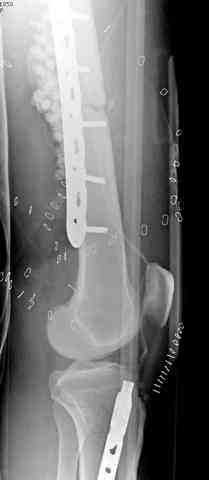

Я бы выполнил более стабильную фиксацию (а у меня есть подозрения в нестабильности отломков - компоновка минимальная, стержни проведены близко друг от друга, имеется выраженное воспаление тканей вокруг раны). Добавил бы стержни в данном аппарате или бы наложил спицестержневой аппарат.

Наверное, оптимальное решение для закрытие раны на данном неудобном уровне - микрохирургическая пересадка мышечного или кожно-мышечного лоскута (рис. 1, 2, 3).

Если поблизости нет микрохирургов - то можно сделать пластику лоскутом камбаловидной мышцы (distaly based hemisoleus) или латеральным надлодыжечным лоскутом (lateral supra malleolar flap, его минус в том что он не имеет мышечного компонента). У меня нет иллюстрации по закрытию камбаловидной мышцей на данном низком уровне - нижняя треть голени (хотя о локализации раны трудно судить из приведенных иллюстраций), но на уровне средней трети голени мы имеем около десятка операций с очень хорошим результатом (рис. 5, 6, 7).

Надеюсь, Вам помогут иллюстрации из AO Principles of Fracture Management (2000 г.) - (рис. 8, 9, 10).